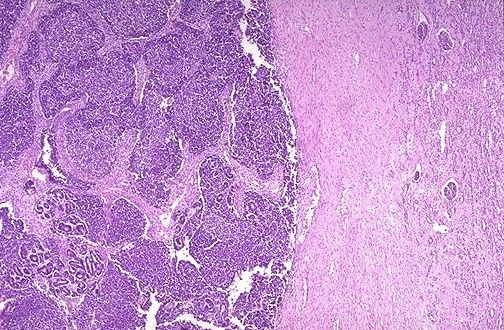

| Tumor de Wilms |

Image:

Renal057 (image/jpeg)